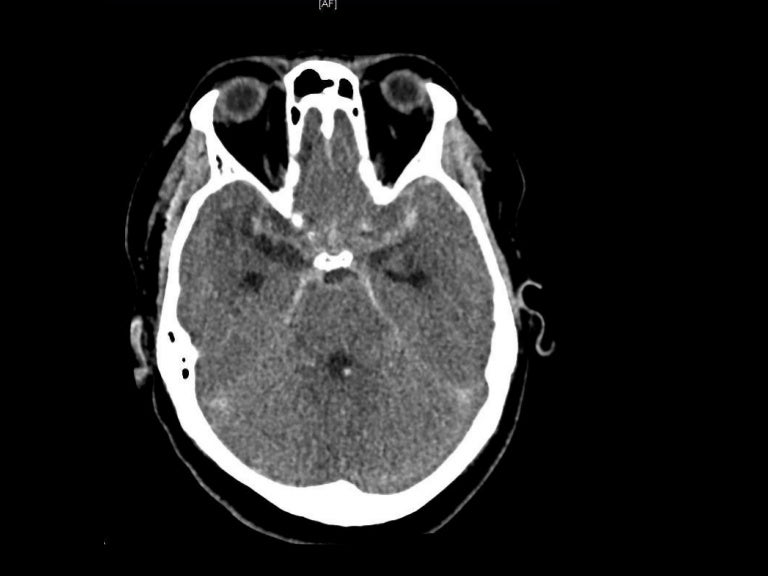

Subarachnoid Hemorrhage (SAH) EMCrit Project What Is Medical Term Sah People who survive an sah may be left with disability. A subarachnoid hemorrhage (sah) is bleeding in the area surrounding the brain called the subarachnoid space. A subarachnoid haemorrhage is an uncommon type of stroke caused by bleeding on the surface of the brain. Subarachnoid haemorrhage (sah) describes bleeding into the subarachnoid space of the brain, which is located between. What Is Medical Term Sah.

CT brain image gallery SAH What Is Medical Term Sah When this occurs, blood fills the space between the brain and. People who survive an sah may be left with disability. Sometimes, bleeding is caused by trauma, a tangle of blood vessels in the brain (arteriovenous malformation), or other blood. It's a very serious condition and. A subarachnoid haemorrhage is an uncommon type of stroke caused by bleeding on the. What Is Medical Term Sah.